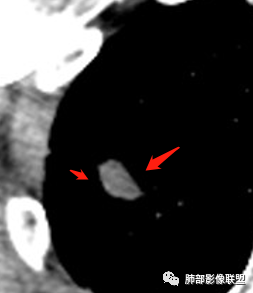

增强扫描右肺尖结节强化不明确,但左肺尖后段结节出现了典型的环形强化

右肺上叶结节灶,边缘膨隆,有毛刺,胸膜牵拉,轻度强化,左肺上叶结节灶环形强化,左肺考虑结核,右肺结节灶,不排除疤痕癌。

两肺上叶结节影,右肺结节边缘清晰,平直,有胸模牵拉,有卫星灶,强化不明显,左肺结节周边强化,两肺门淋巴结肿大,整体考虑结核。

中老年男性,体检发现双肺尖结节,边缘长索条,邻近胸膜粘连,病灶收缩力不太强,右肺尖病变周围少许卫星灶,增强后环形强化表现,首先考虑结核,治疗后复查

两上肺(右尖左尖后)都有小结节影,右肺尖结节边缘可见卫星灶,结节边缘平直凹陷、长毛刺,部分膨隆,增强扫描右肺尖结节强化不明确;左肺尖后段结节边缘平直凹陷,增强见环形强化。考虑结核可能性大,右上肺注意鉴别腺癌。

左肺的边缘强化明显

左上叶结节,环形强化,考虑肉芽肿病变,结核可能,右上叶结节,中度强化,有长毛刺,胸膜牵拉,有刀切征,考虑肉芽肿病变,腺癌待排,建议抗炎后复查或穿刺活检。